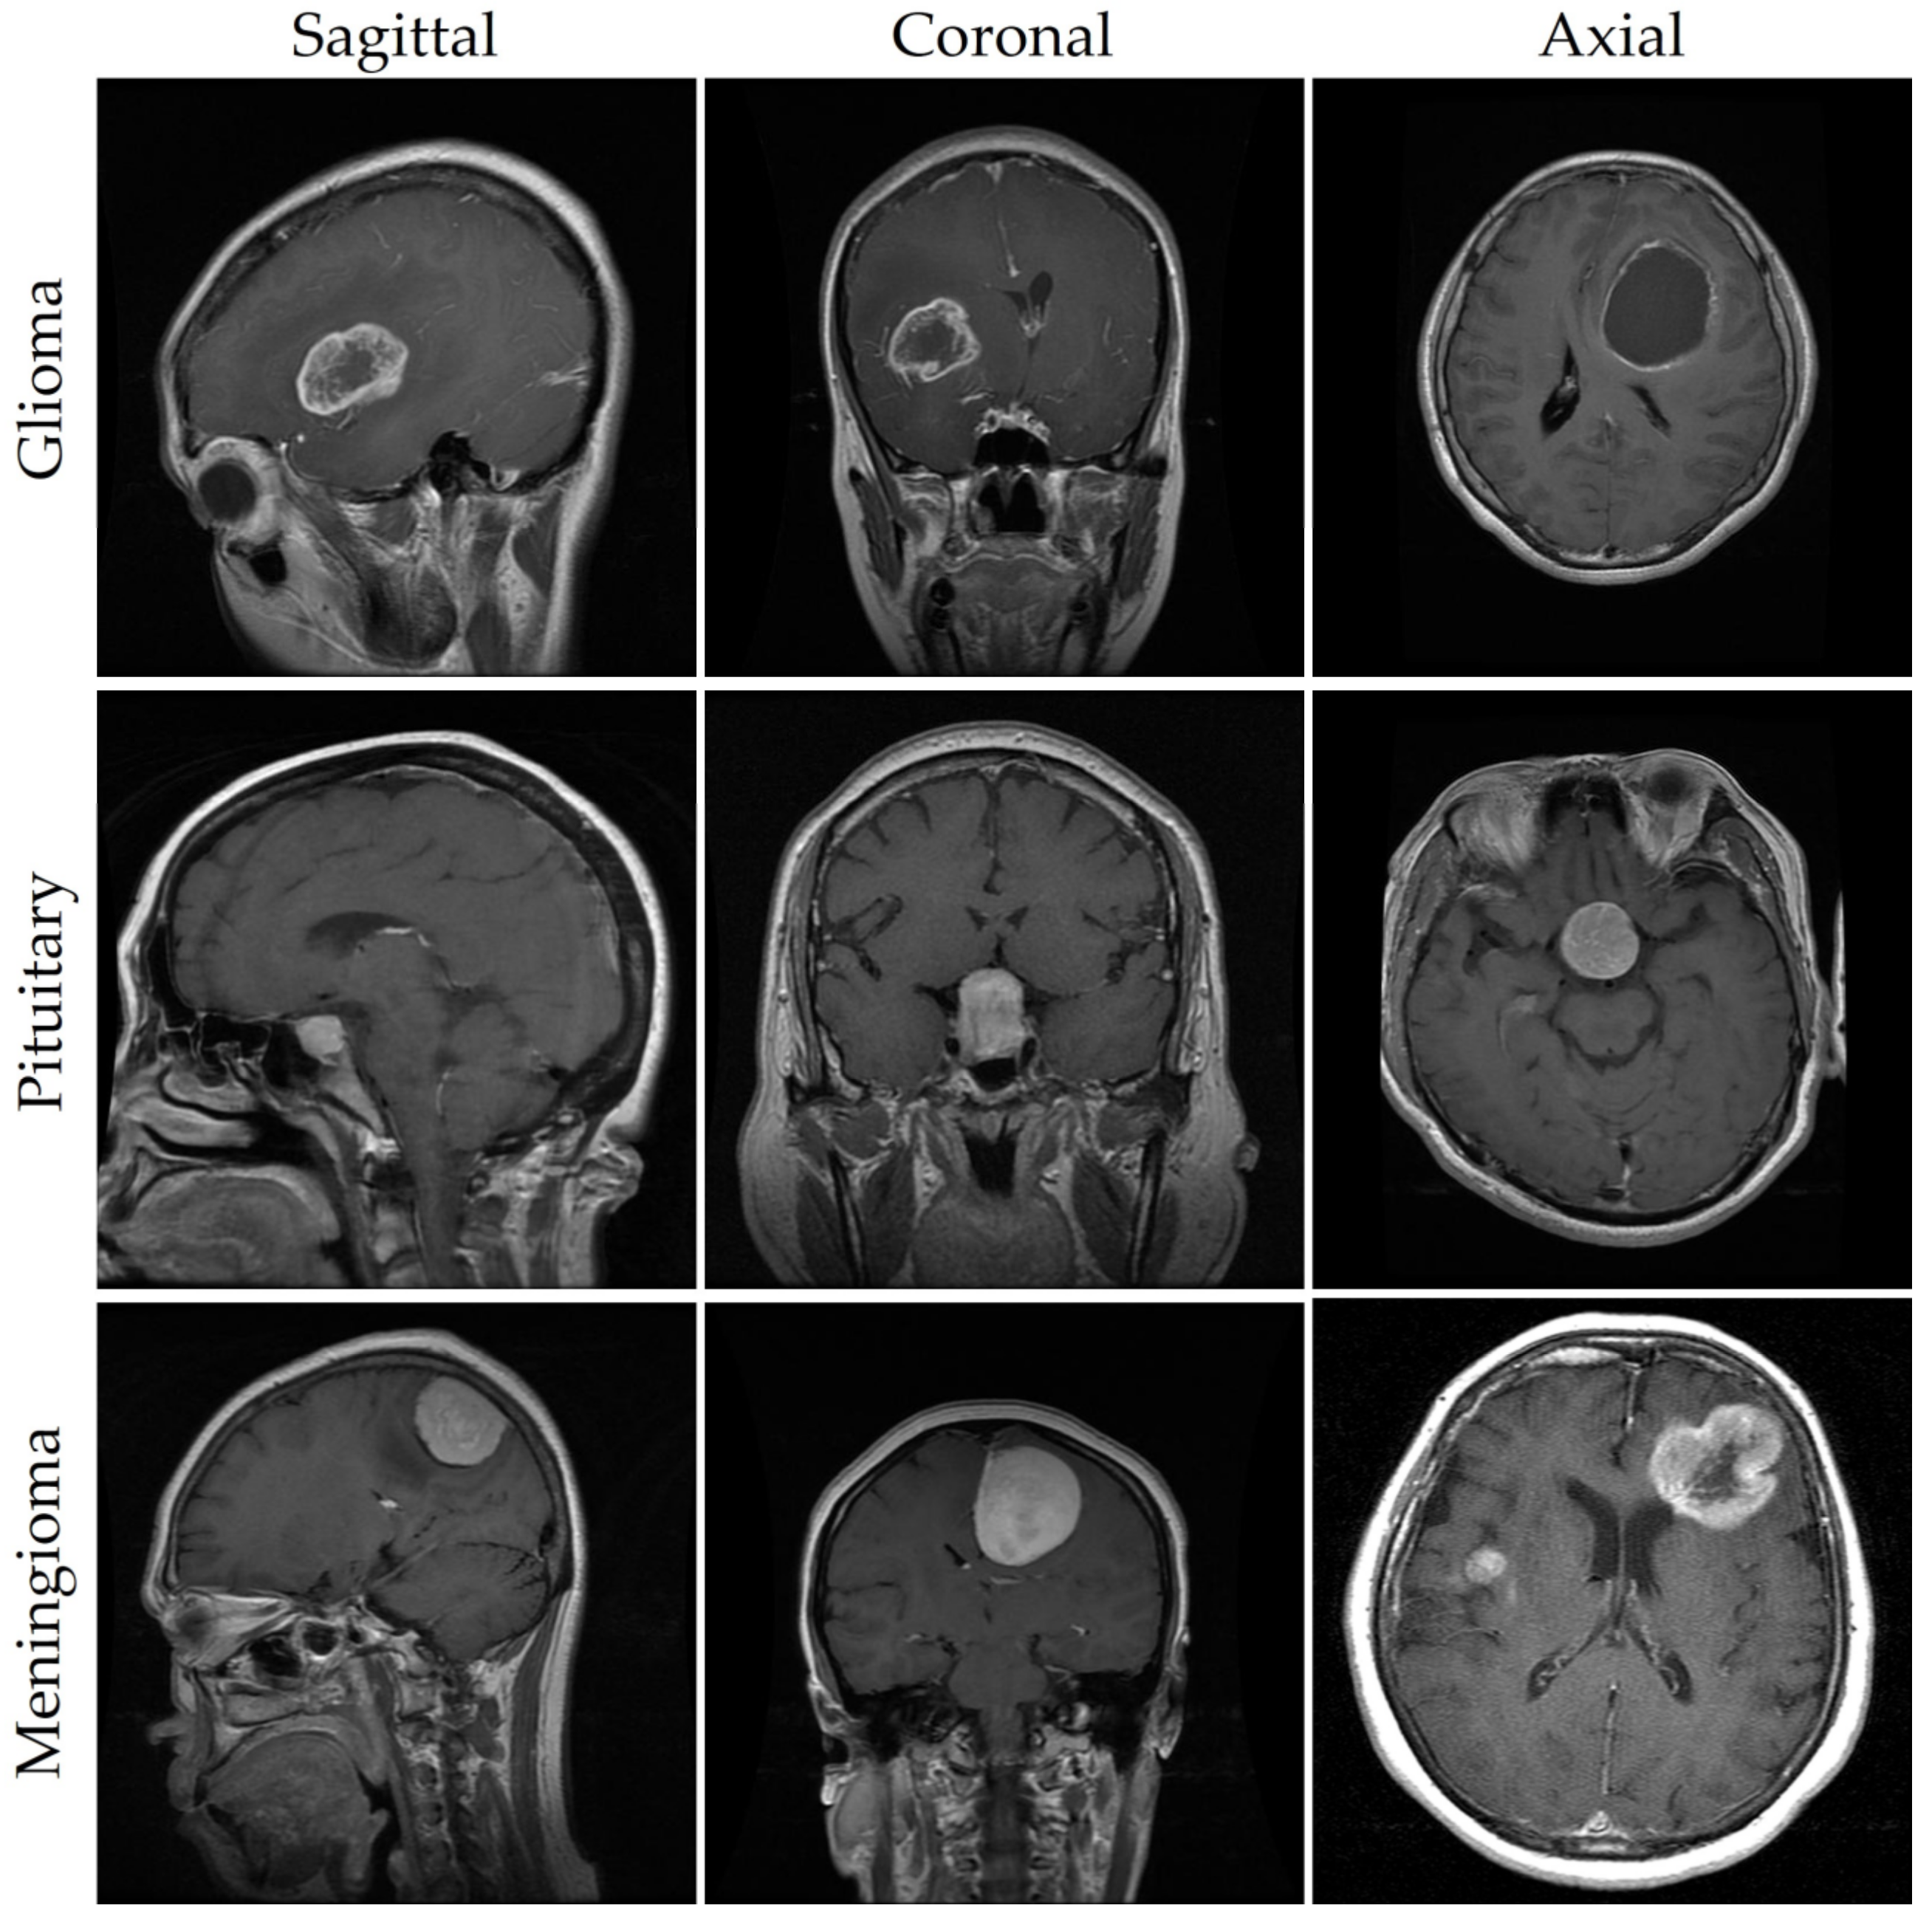

As seen in Figure 1 and described in [9], meningioma, glioma, and pituitary tumors are the most frequent primary brain tumors seen in clinical practice. Most cases of meningioma arise near the meninges tissues on the periphery of the brain or spinal cord [10]. This benign tumor develops in the membranes that rescue the brain and spinal cord. However, glioma, the brain tumor with the highest fatality rate [11], develops from the glial cells that surround and support the neurons. About a third of all cases of brain tumors are gliomas. Benign pituitary tumors develop inside the pituitary gland [12]. Prognosis and treatment options for brain tumors depend on a correct diagnosis. However, conventional biopsy techniques are painful, time-consuming, and fraught with inaccuracy in sampling [13,14]. Histopathological tumor grading (Biopsy) has its own set of problems, including intra-tumor heterogeneity and differences in the subjective assessments of different experts [15]. The diagnostic process for tumors is made more difficult and restrictive by these characteristics.

Effective treatment planning and patient outcomes depend on a quick and precise diagnosis of brain tumors. However, radiologists may spend a lot of effort on image analysis when dealing with brain tumors [16]. Today’s radiologists must rely on their own skills and subjective interpretation of pictures to make detection and decisions manually [17]. Accurate diagnosis by human visual examination alone is difficult due to the wide range of practitioners’ expertise and the inherent complexity of brain tumor images [18]. MRI scanning is commonly utilized in neurology because it allows for an in-depth examination of the skull and brain [19]. It provides axial, coronal, and sagittal imaging for a more thorough evaluation [20]. In addition to producing high-resolution pictures with great contrast, MRI also has the benefit of being a radiation-free technology. For this reason, it is the preferred noninvasive imaging technique for identifying many forms of brain malignancy [21].

To ensure the validity of our findings, we used an openly available MRI dataset obtained from kaggle.com [64,65]. MRI scan images are included in this collection, since they are the gold standard for diagnosing brain tumors. Glioma (2548 images), pituitary (2658 images), meningioma (2582 images), and no tumor (2500 images) were the four subsets that made up our dataset of brain tumors. Images were all scaled to 512 pixels on the horizontal and vertical dimensions. We used 8232 MRI images (or 80% of the dataset) for training in our analysis, whereas 2056 MRI images (or 20% of the dataset) were set aside for testing. Brain tumor photos from various categories are shown as examples in Figure 1. For each type of brain cancer (glioma, pituitary, and meningioma), Table 1 provides the number of pictures in various views such as axial, coronal and sagittal. It is important to keep in mind that medical photos, in contrast to natural images, are more complicated and necessitate a greater level of skill to ensure appropriate analysis and interpretation. The brain tumor dataset was labeled with oversight from a medical specialist to ensure precision and consistency. This physician’s expertise was crucial, as it established criteria for how the dataset should be labeled. However, not all brain cancers have characteristic imaging findings; therefore, depending entirely on image analysis can be risky. As a result, pathology analysis is essential for diagnosing brain cancers. Our dataset featured abnormal language descriptions annotated by a medical expert to give rich context for model training. A larger amount of training data aids in the creation of more reliable models. Data augmentation strategies can be used to increase the diversity of the training samples when the volume of available data is low. To improve a model’s generalizability, data augmentation can be used to generate new variants of the existing data. In conclusion, our model’s predictive power was enhanced by the incorporation of extensive labeled data, curated by medical experts. To further improve the prediction models’ accuracy and reliability, data augmentation techniques can be used to increase the diversity of the training samples.